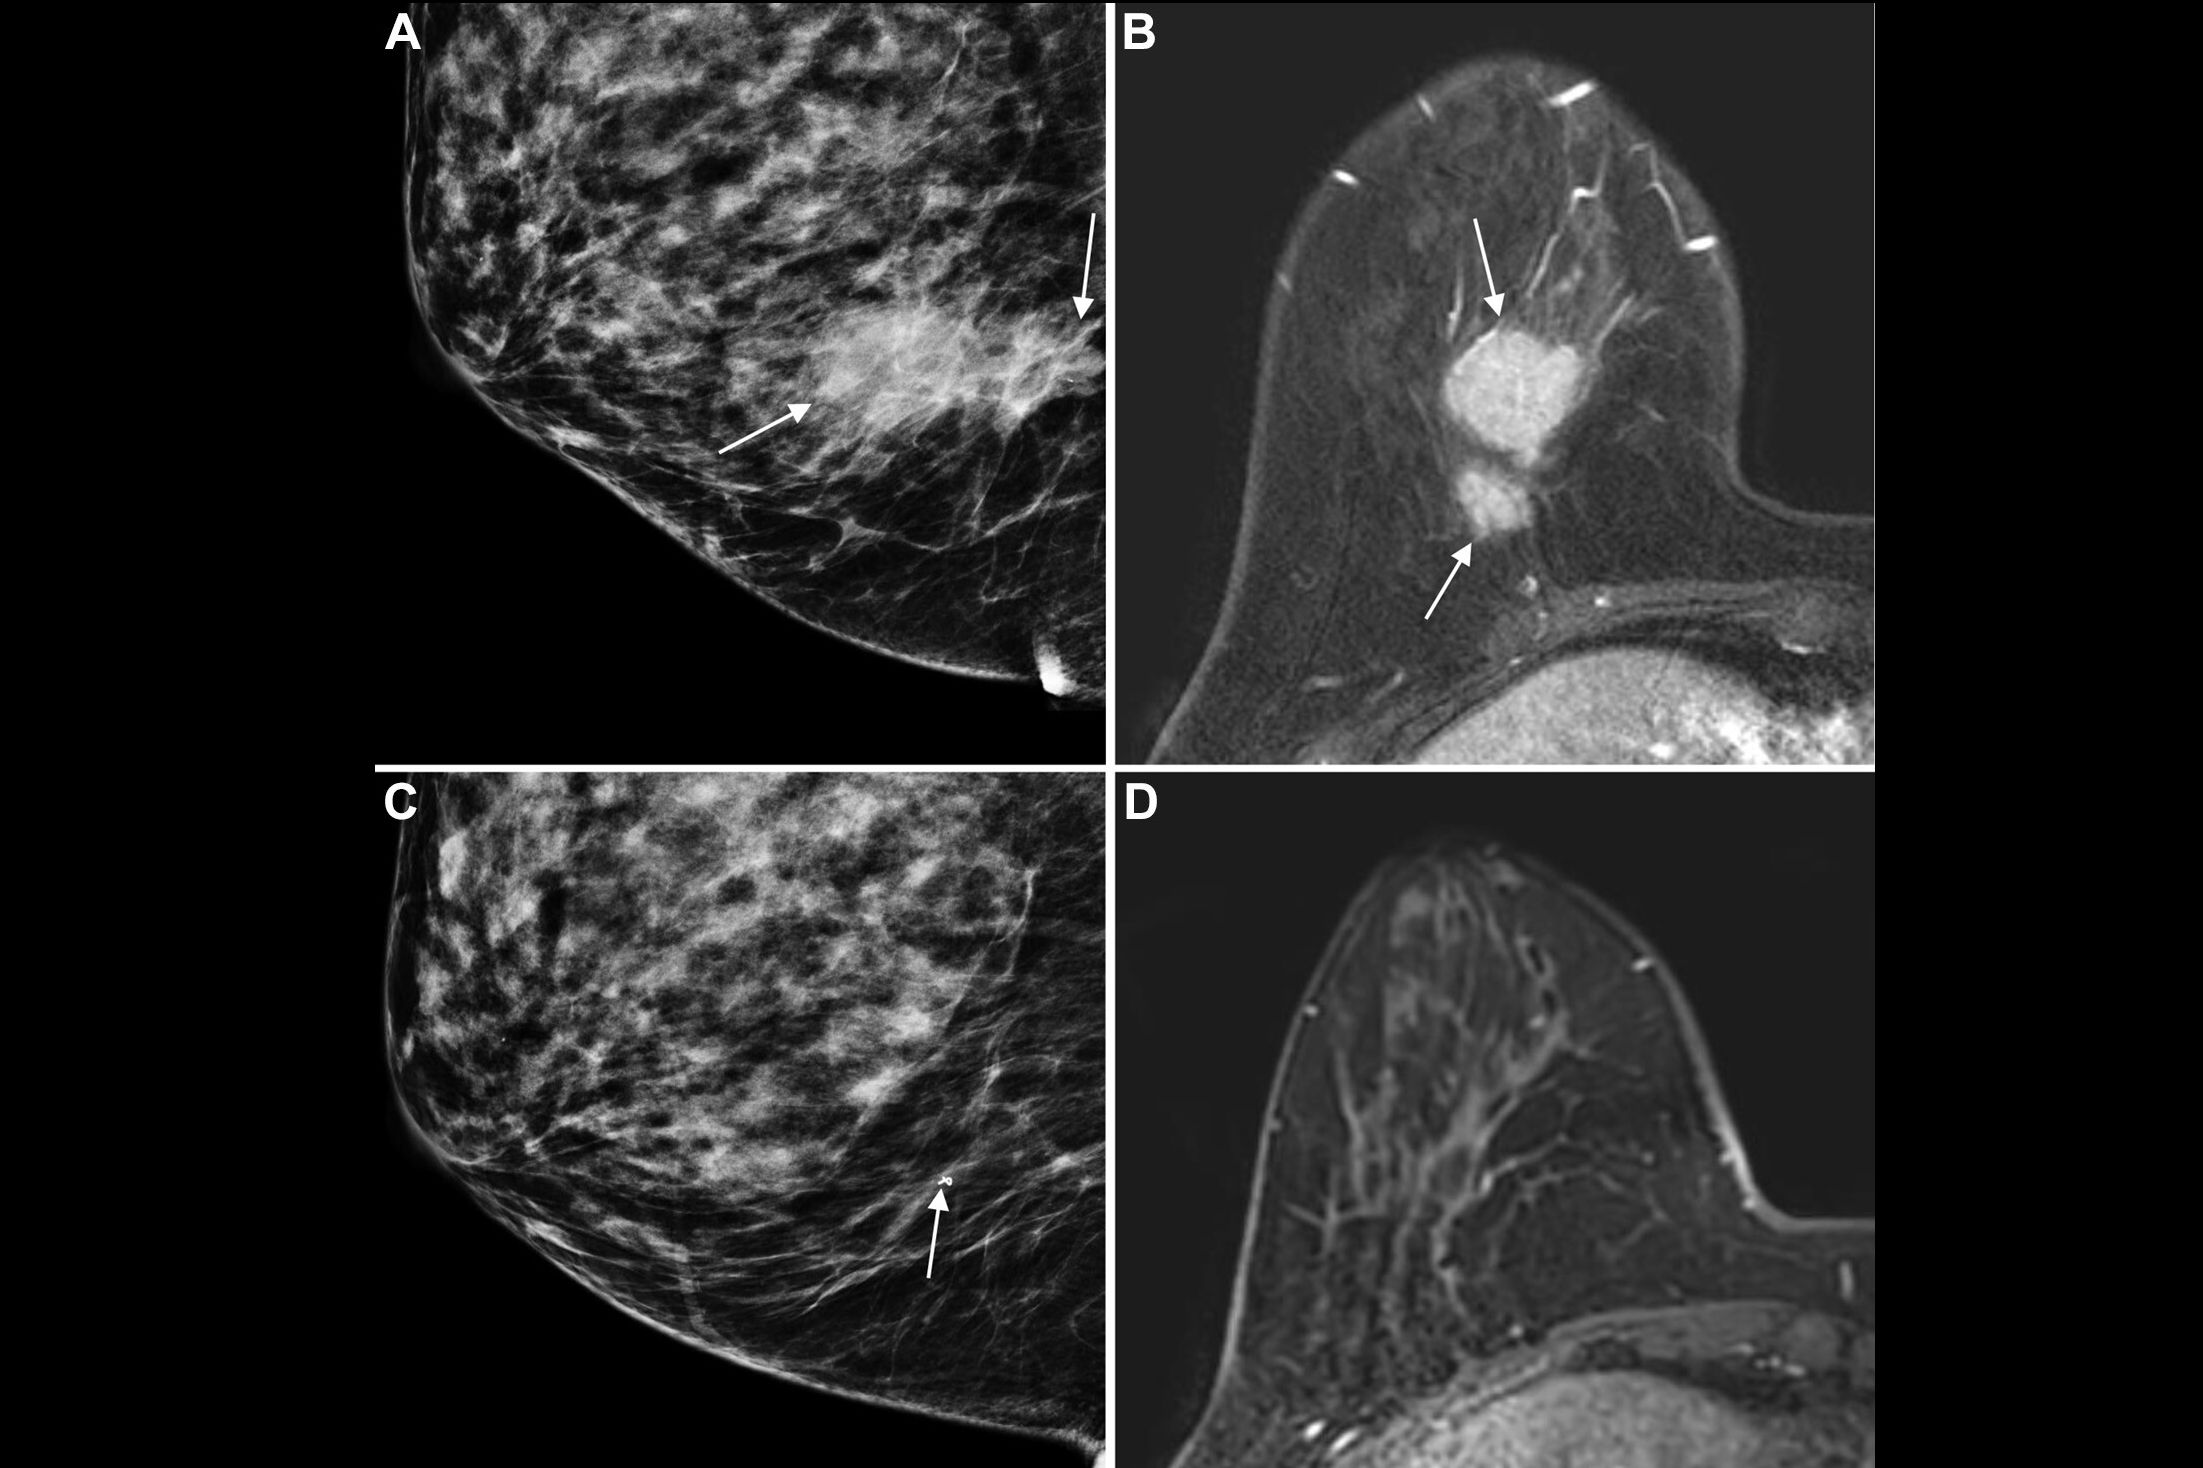

The growing effectiveness of artificial intelligence (AI) software in reading mammography and digital breast tomosynthesis (DBT) exams has been evident in a number of studies published in recent years. And a new meta-analysis encompassing over 1 million screening breast imaging exams has now concluded that the technology's performance is equal to or better than that of radiologists.

While you're there, you can also check out other popular stories, including an article on how AI aided radiologists in diagnosing small invasive lobular carcinoma on breast ultrasound images. Speaking of AI and breast ultrasound, another study found that deep learning-based computer-aided diagnosis software could help radiologists to downgrade a significant number of breast lesions, potentially reducing the number of breast biopsies that need to be performed.